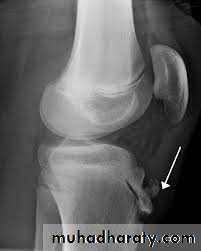

X-ray

The anteroposterior x-ray must be obtained with the patient standing and bearing weight; only in this way can small degrees of articular cartilage thinning be revealed.1-The tibio-femoral joint space is diminished

(often only in one compartment) and there is

2-subchondral sclerosis.

3-Osteophytes and

4- subchondral cysts

5-chondrocalcinosis are usually present and sometimes there is soft-tissue calcification in the suprapatellar region or in the joint

itself

X-ray weight bearing